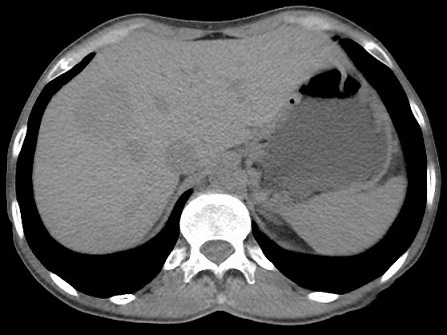

Image TDM de kyste du

foie : Image lesionaire arrondie , de taille variable souvent de

quelque centimetrique . Densite liquidienne de 0

a 15UH

Image radiologique TDM d'une kyste simple

du foie droit en coupe axiale : Aspect

lesionnel a densite variee de 7-15 UH ( hypodense )

avec bord lisse , bien definie et regulier |